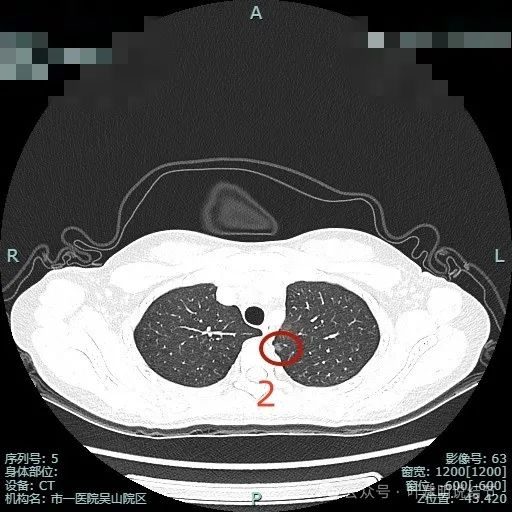

病灶2:左上叶磨玻璃结节,整体轮廓较清,考虑肺泡上皮不典型增生或原位癌可能性大。